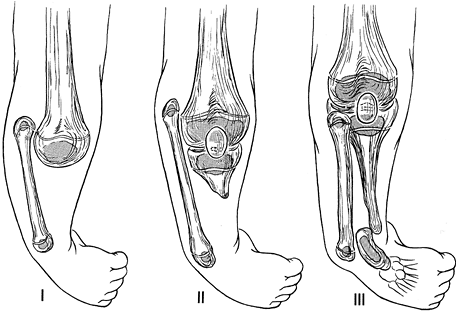

To better characterize the variability, Achterman and Kalamchi (2) refined a classification originally utilized by Coventry and Johnson (18) (Fig. 174.1).

In type IA, the entire fibula is present but shortened, leaving the

the distal fibular physis proximal to the dome of the talus. In type

IB, there is a partial absence of the upper fibula, and the lower

not buttressing the ankle. In type I deformities, the foot usually

joint, and either equinovalgus or equinovarus may be present. In type

II, by contrast, the entire fibula is absent, tibial bowing is

frequent, and ankle instability is the rule. A residual lateral fibrous

band may contribute to the type II deformity.

Figure 174.1. Achterman-Kalamchi classification of fibula hemimelia. See text for explanation.